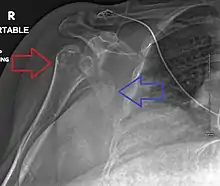

A displaced supracondylar fracture in a child Fracture dislocation of the right shoulder

Fracture dislocation of the right shoulder